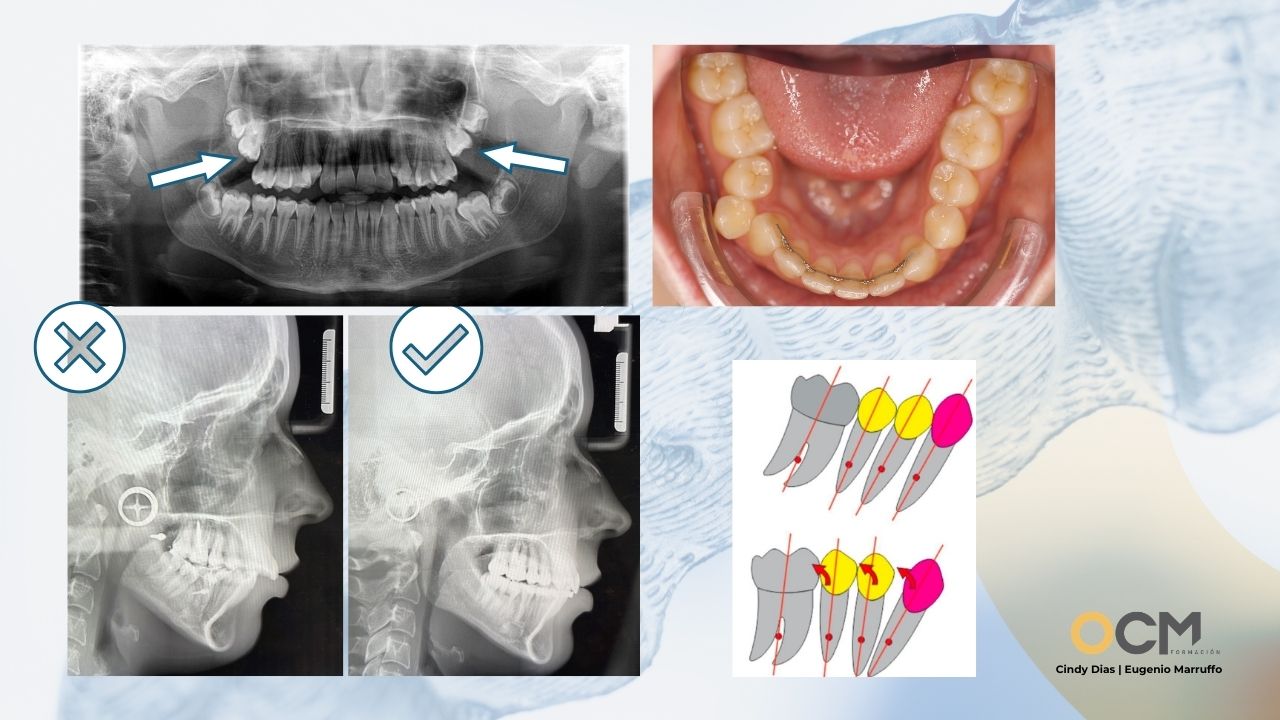

• Fundamentos: Función cráneo-mandibular y principios de oclusión.

• Protocolo NOWA: Ortodoncia cráneo-mandibular con alineadores

• Desarrollo Transversal (considerando anatomía y fisiología)

• Alineación y Nivelación Estratégica

• Reposicionamiento mandibular

• Control del plano oclusal

• Aumento de dimensión vertical